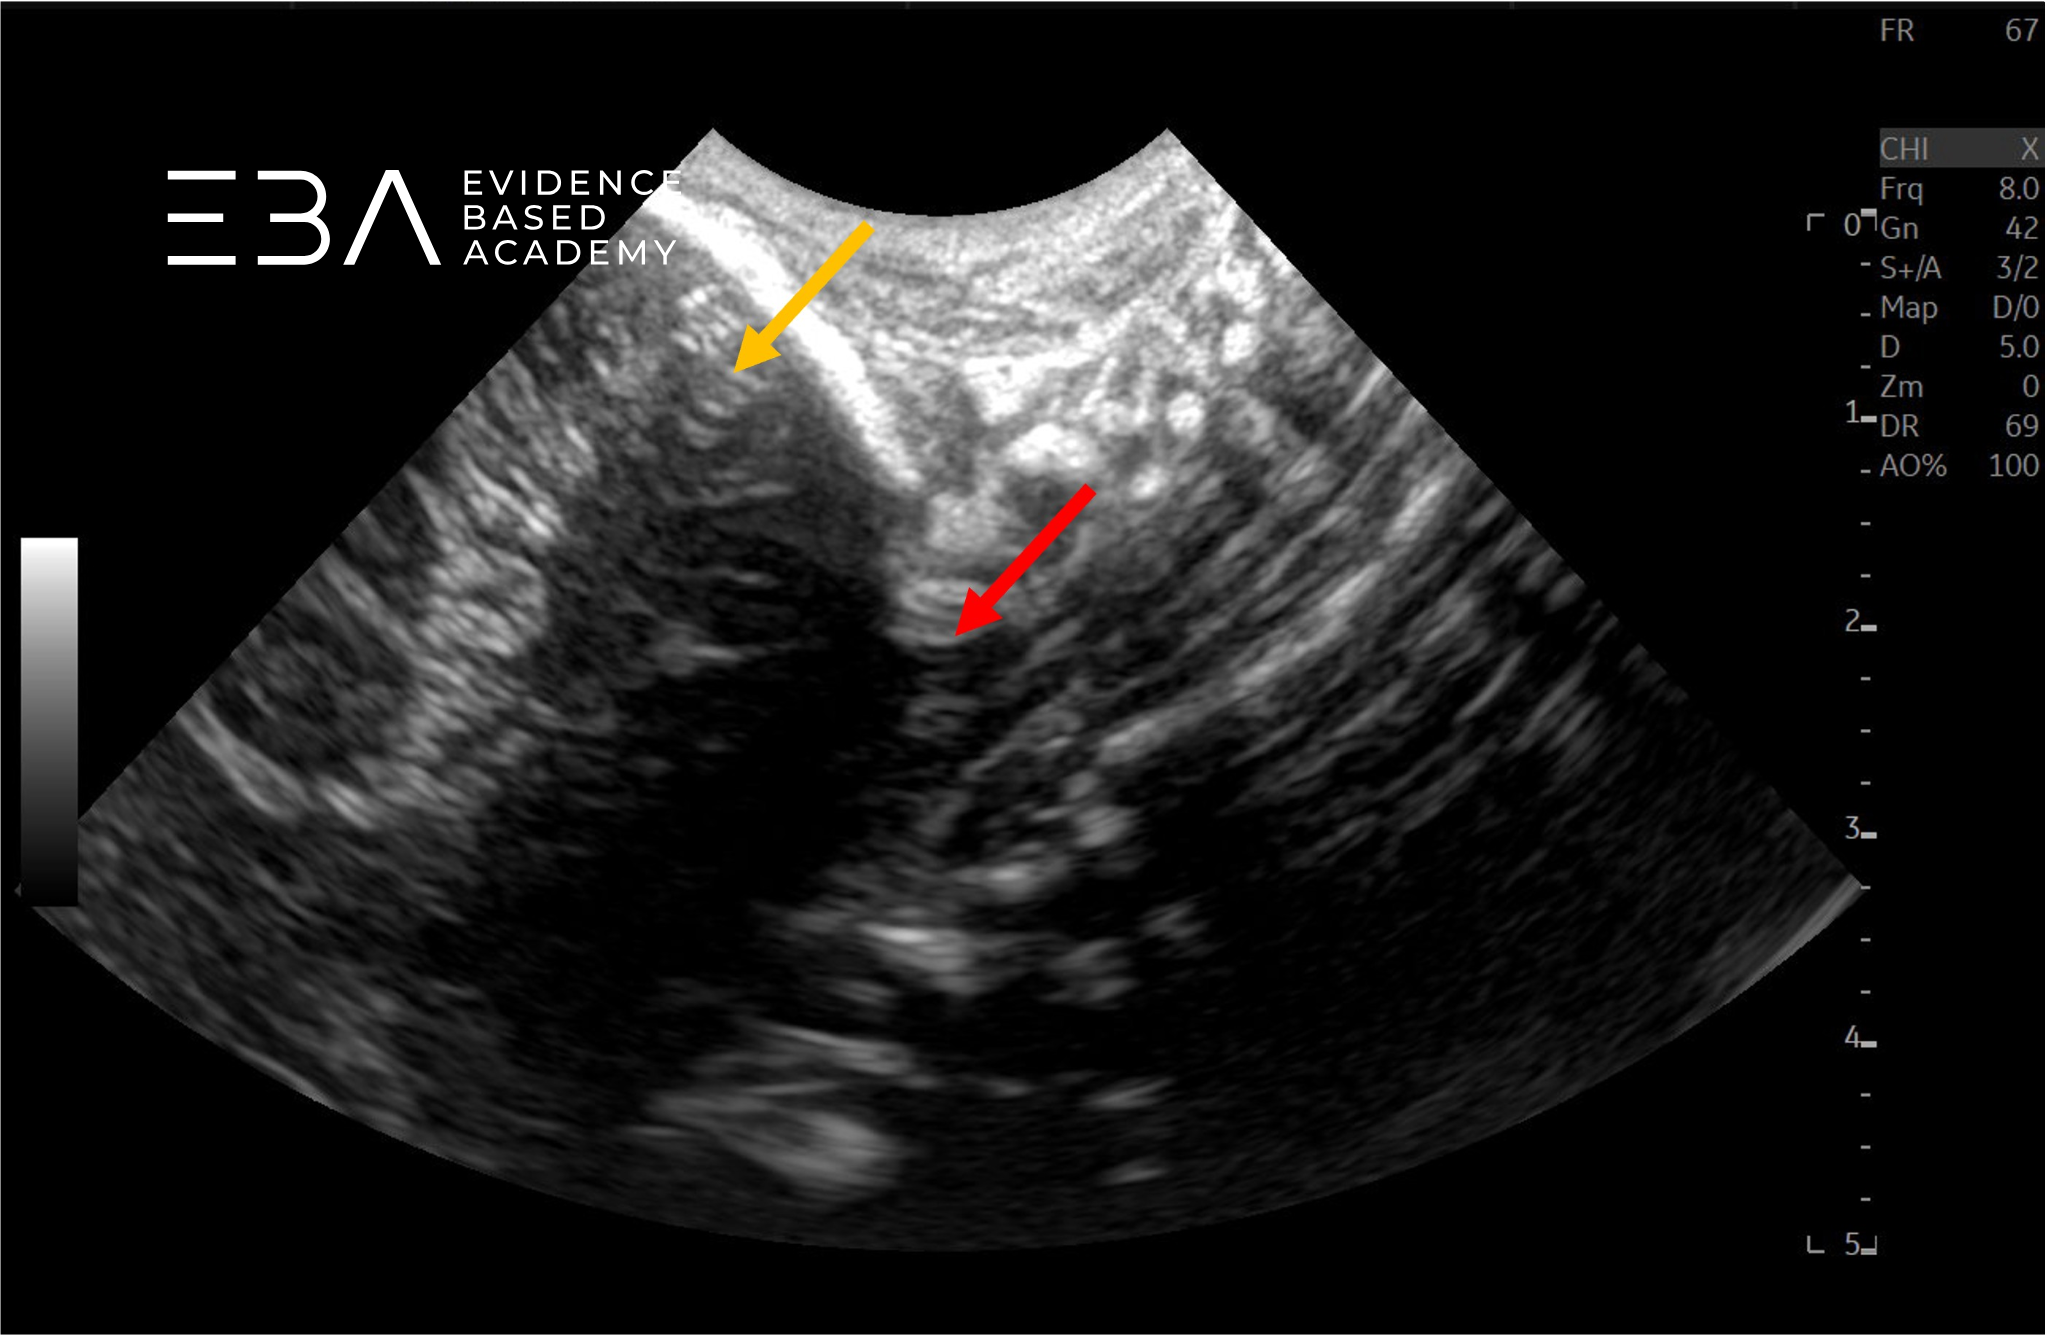

fot. 2

Przekrój podłużny kanału kręgowego w odcinku szyjnym, głowica mikrokonweksowa. Czerwoną strzałą zaznaczono rdzeń kręgowy, pomarańczową strzałą móżdżek.

fot. 3

Przekrój podłużny kanału kręgowego w odcinku szyjnym, głowica mikrokonweksowa. Czerwoną strzałą zaznaczono otwór wielki, pomarańczową strzałą móżdżek.